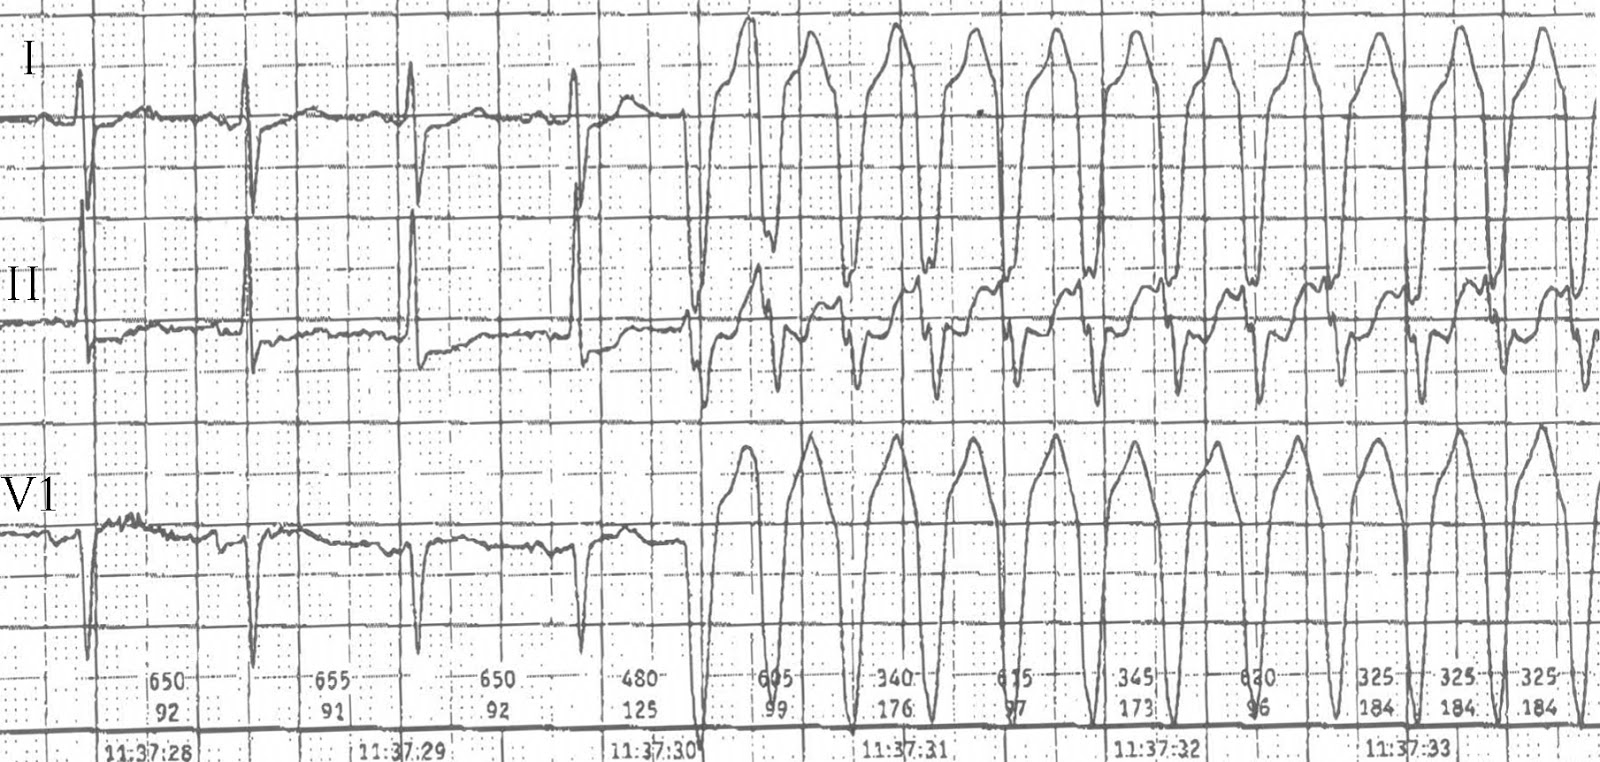

Další v nové sérii EKG video kazustik. Tentokrát se podíváme na matoucí záznam z EKG Holter monitorace, který nám přišel ke konzultaci a „zvážení dalšího postupu“ od ambulantního kardiologa.

Je na EKG supraventrikulární tachykardie s aberantním převodem na komory, nebo komorová tachykardie?